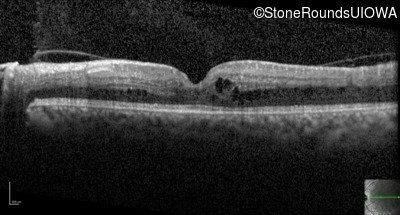

Optical Coherence Tomography - Right - Count Fingers 2'

Exemplar / OCT Stack

OCT Stack